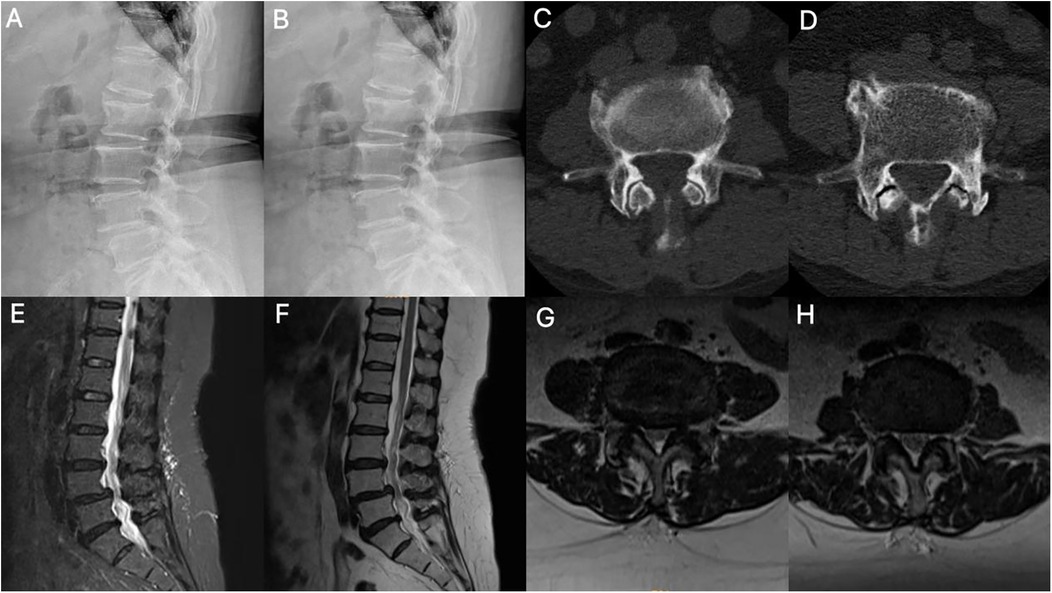

Figure 1. Imaging findings. (A,B) Dynamic lumbar radiographs demonstrate instability with spondylolisthesis. (C,D) Axial CT of the lumbar spine showed segments L3–4 and L4–5 with degenerative changes and lumbar disc herniation. (E-H) MRI shows disc herniation, folded ligamentum flavum causing pincer-type compression of the cauda equina, facet joint hypertrophy, and spinal canal stenosis.